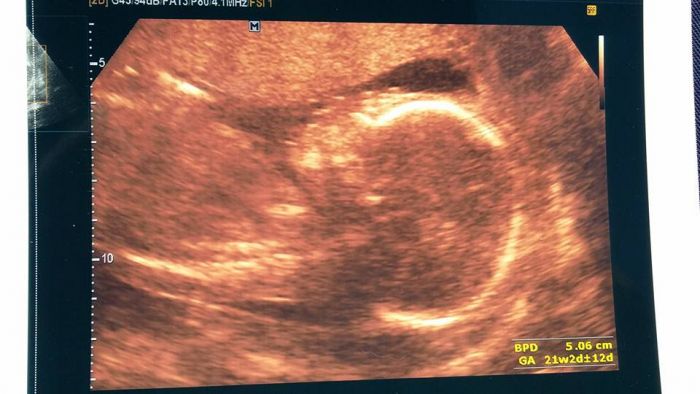

ahoj, holky, doma to teď není jednoduché, ale nechce se mi o tom tady ani psát. Snažím se držet se hlavně kvůli miminku a potřebuji už opravdu jen pozitivní zprávy, protože psychicky je to teď dost špatné. Ale byli jsme včera na velkém utz a vše je v pořádku, malý je prostě nádherný. Měří 23cm a váží 400g. Já už mám hezké bříško, které v uplých šatech jde krásně vidět, ve volnějších to ale někteří kolegové ani nezaznamenali